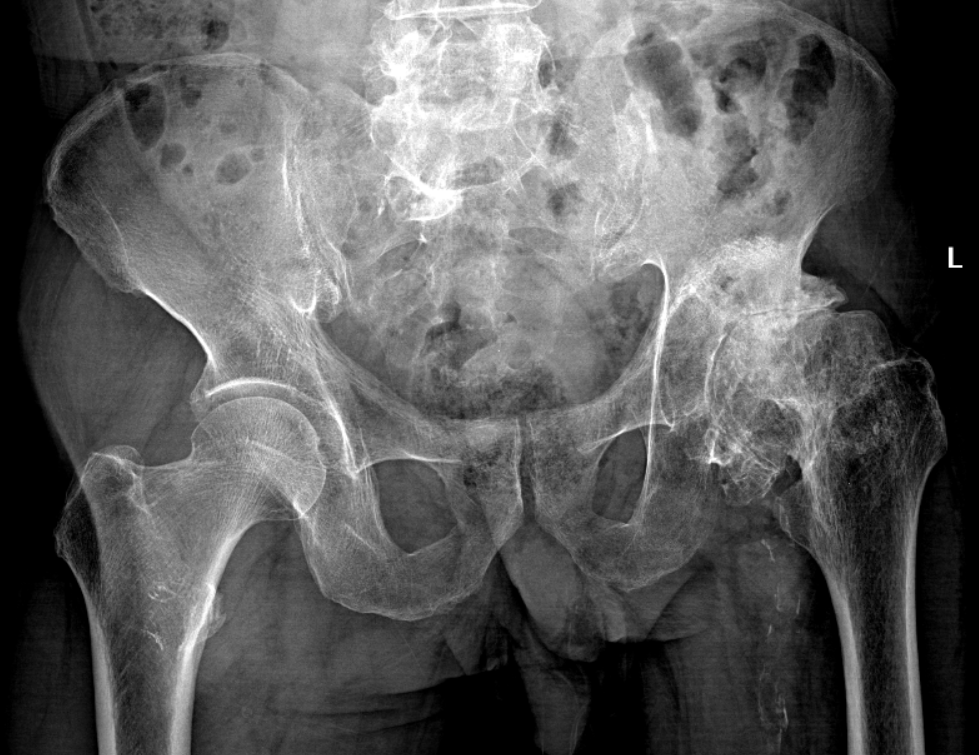

他来到桂林医科大学第一附属医院关节与运动医学科就诊,接诊医生胡译文副主任医师为唐先生进行全面评估,发现唐先生的股骨头已出现塌陷,最终确诊为 酒精性股骨头坏死,坏死程度属于终末期。

股骨头坏死早期,X 光片很可能「看不见」。磁共振(MRI)是捕捉早期信号的「火眼金睛」。我们建议有长期饮酒史或激素使用史的高危人群,每年进行一次髋关节 MRI 筛查。一旦在 ARCO I-II 期(未塌陷)发现,完全有机会保髋治疗手段,避免走到关节置换这一步。